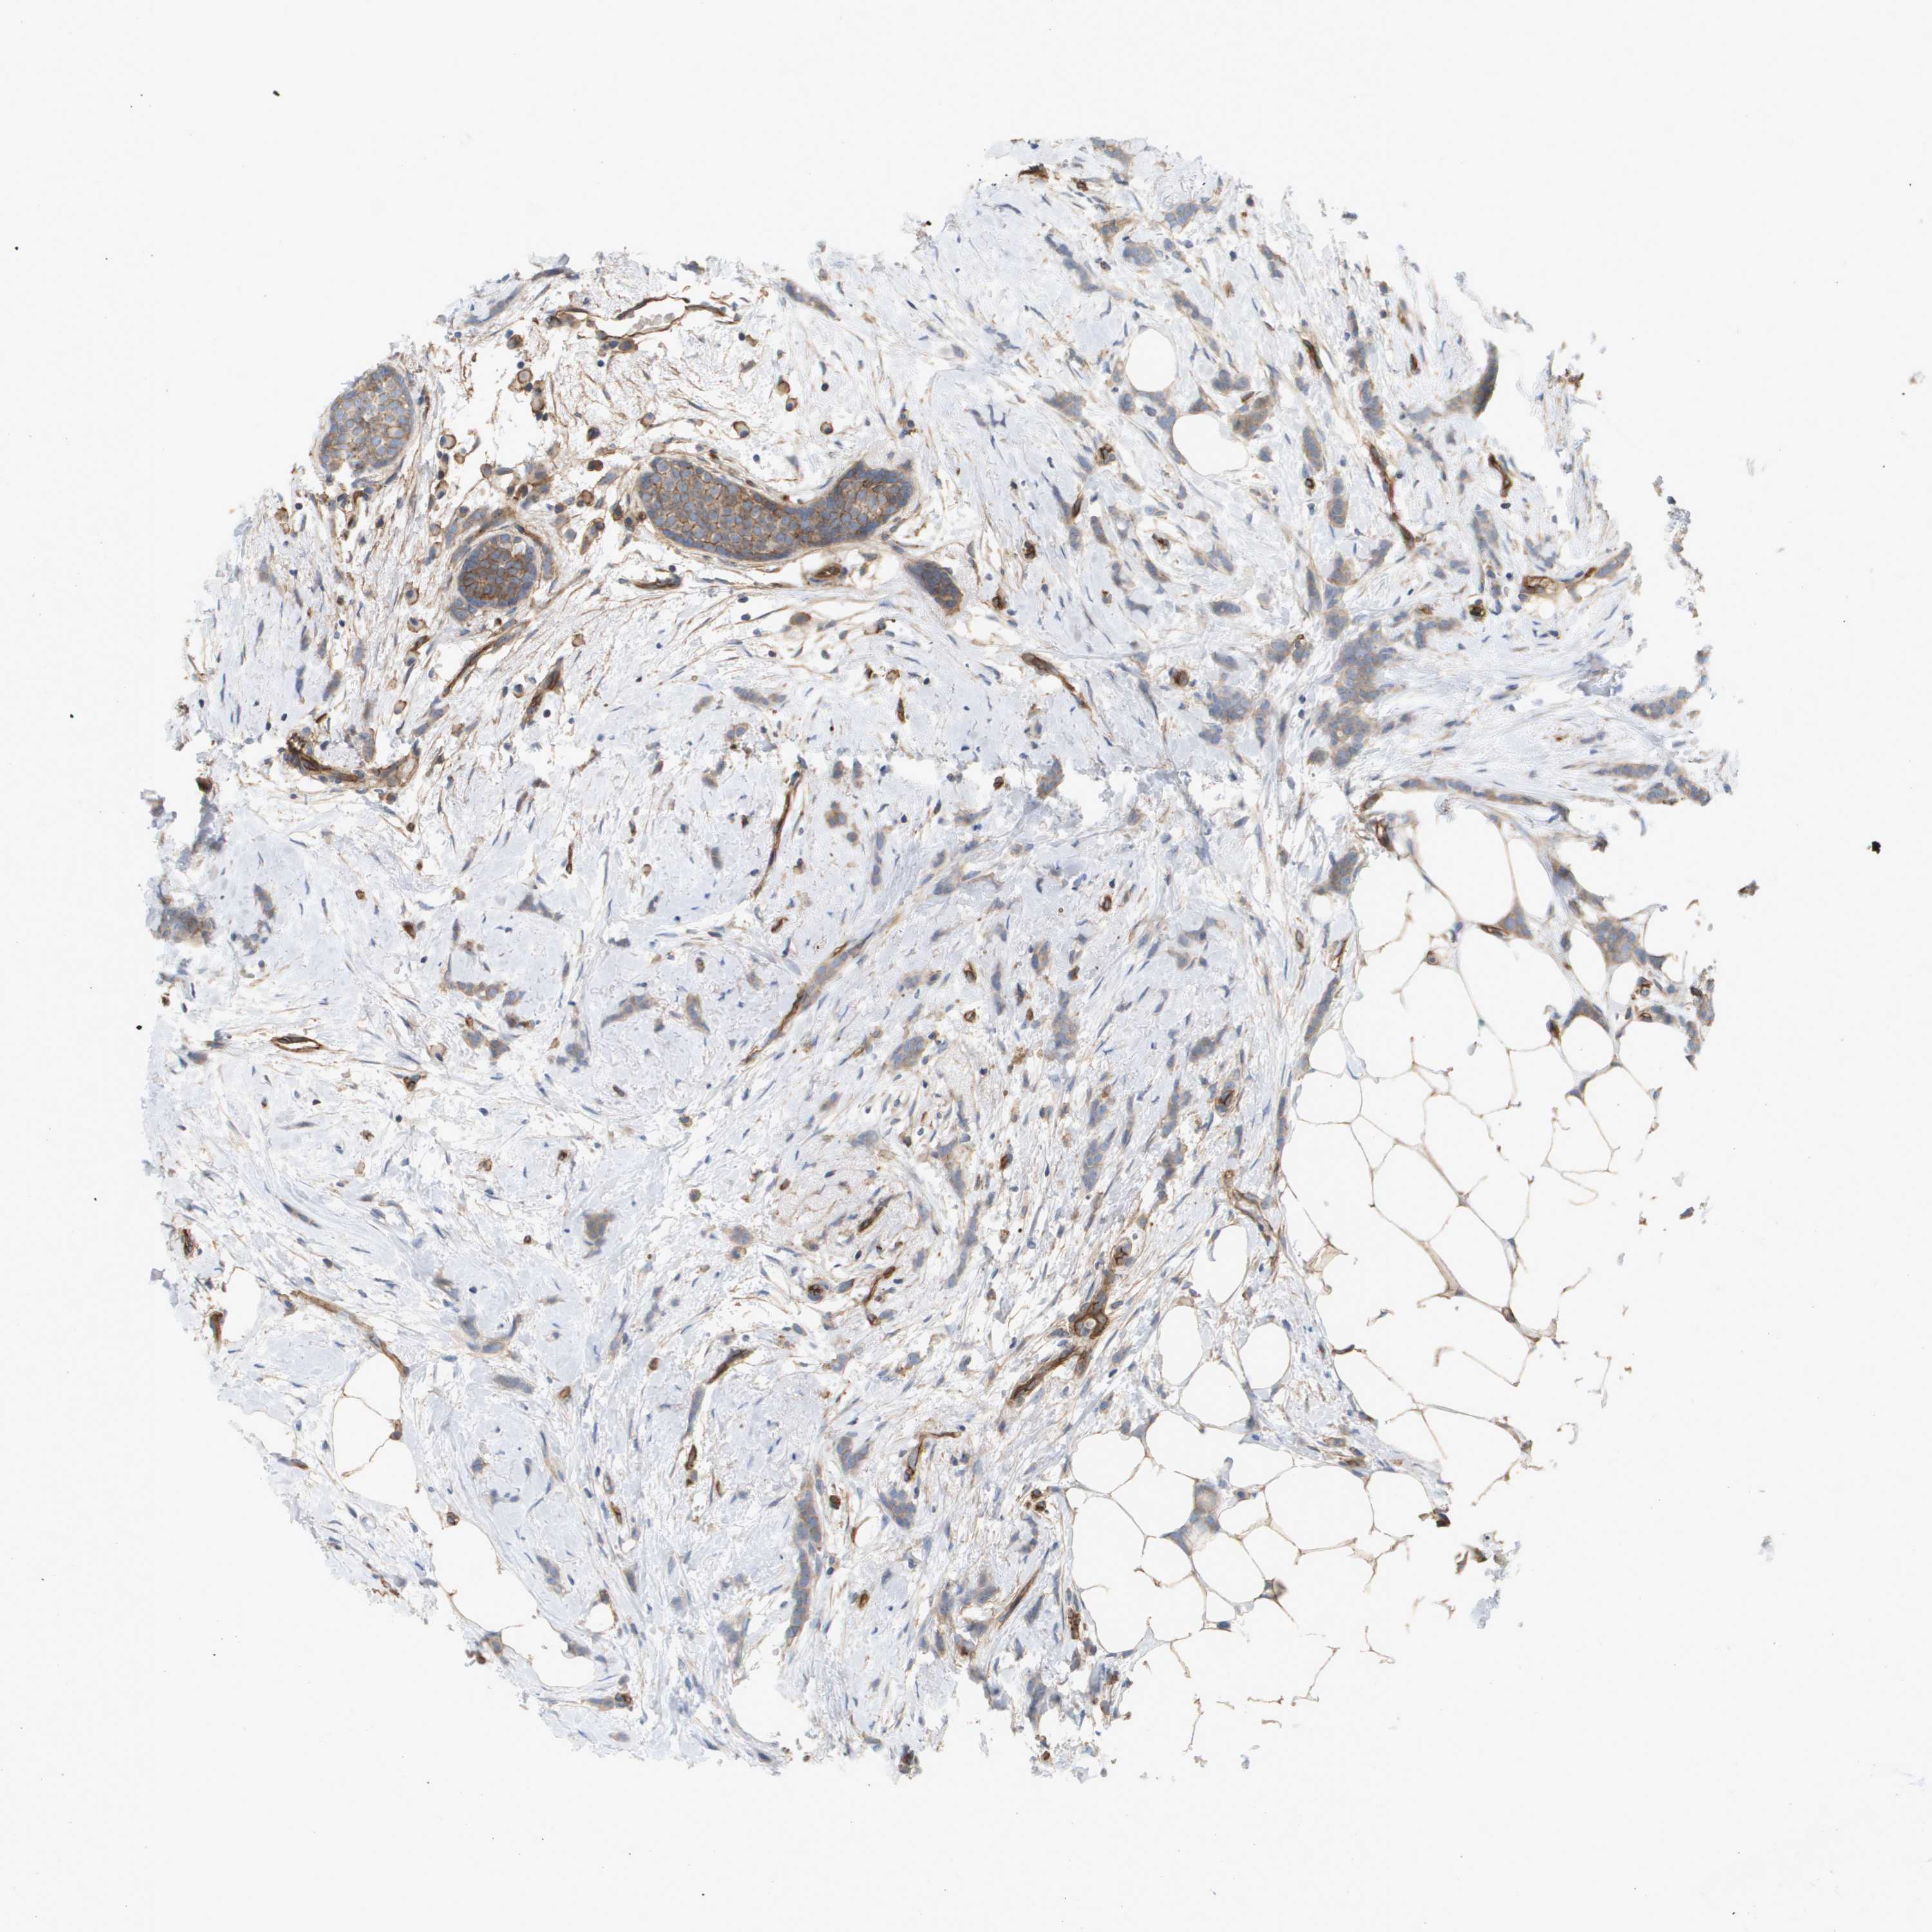

CANCER BREAST CANCER Show tissue menu

BRCA TCGA BRCA VALIDATION PROTEIN EXPRESSION